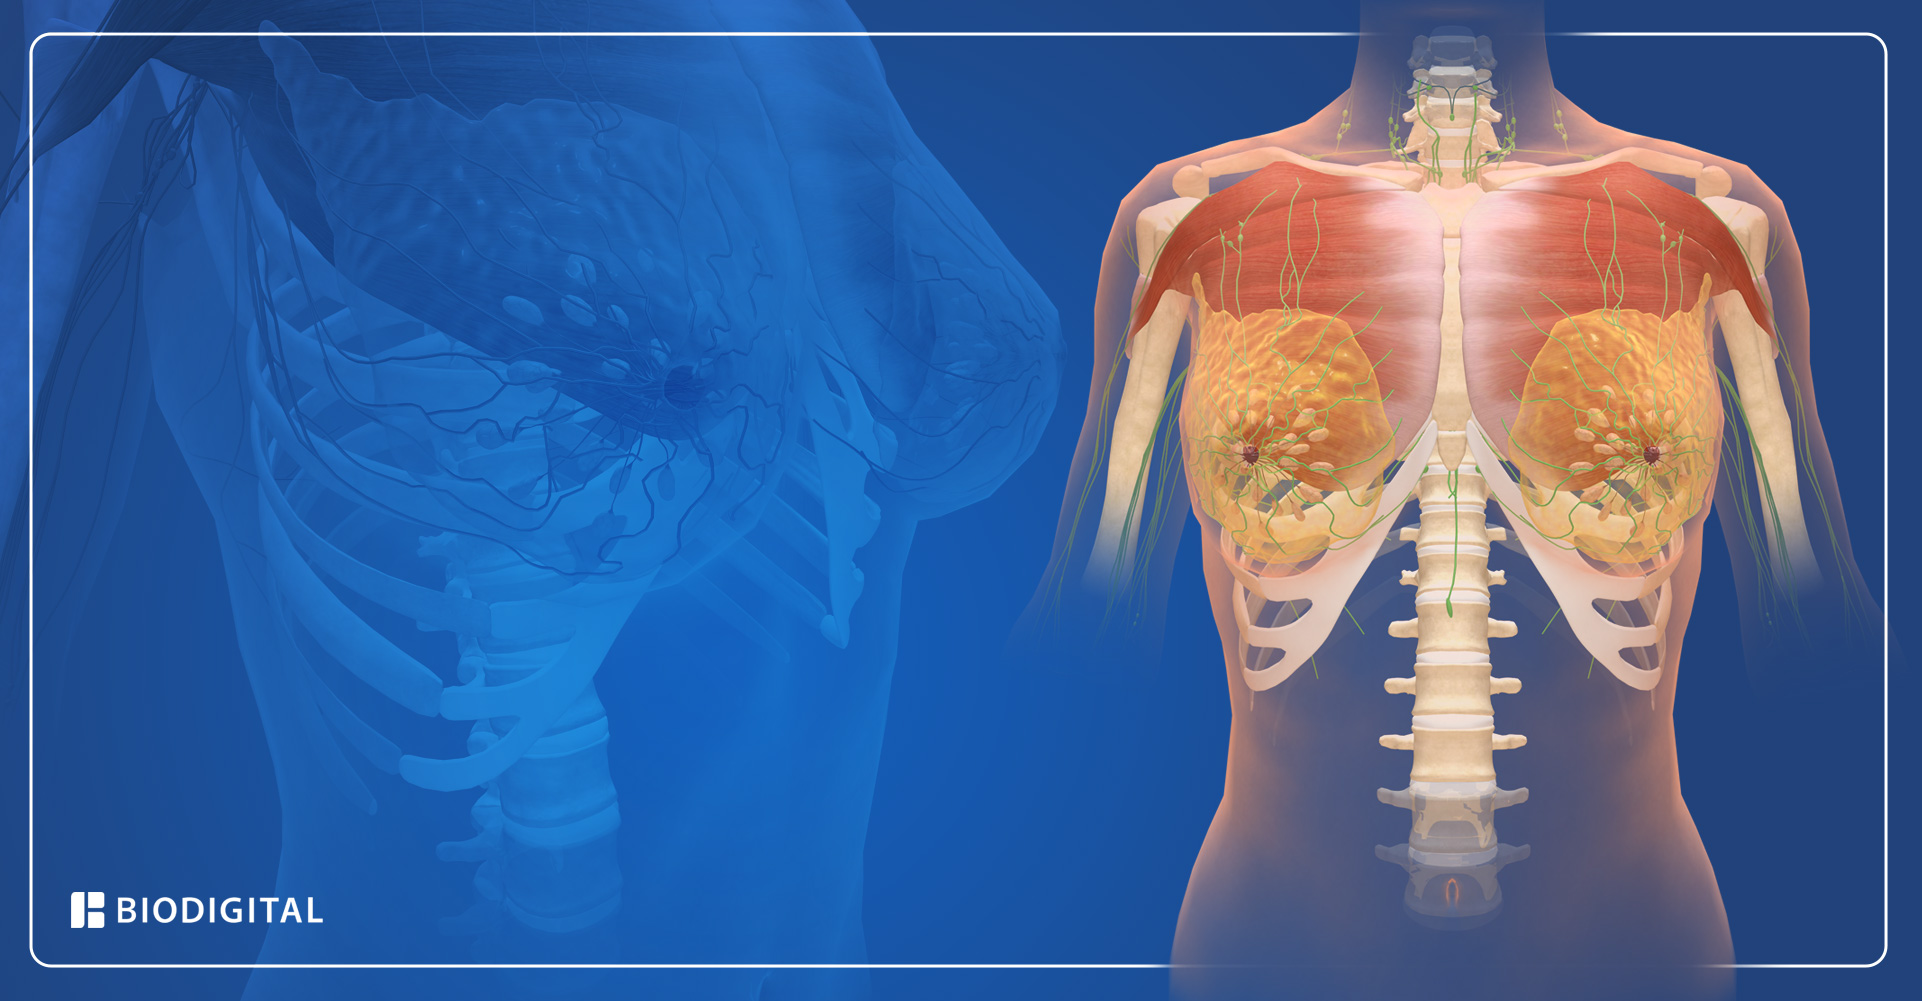

Sistem TNM (Tumor, Node, Metastasis) digunakan untuk menentukan stadium kanker payudara. Sistem ini mengklasifikasikan penyakit berdasarkan ukuran tumor, penyebaran ke kelenjar getah bening, dan adanya metastasis ke organ lain.

Huruf T menunjukkan ukuran dan penyebaran lokal tumor. Huruf N menunjukkan keterlibatan kelenjar getah bening. Huruf M menunjukkan adanya metastasis.